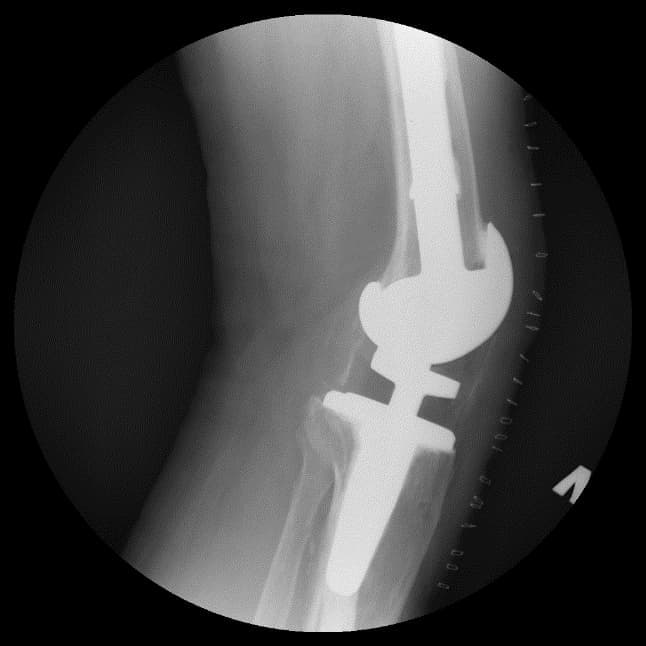

Үе дайрсан ясны анхдагч хавдар, ясны дутмагшлын үед хийгдэх мэс засалimg17Үе дайрсан ясны анхдагч хавдар, ясны дутмагшлын үед хийгдэх мэс засалimg18

Зураг 1. Сэргээн засах мэс заслын өмнөх рентген зураг. Эгц урд, хажуугаас авсан байдал.

Зураг 3. Мэс заслын дараах рентген зураг. Эгц урд, хажуугаас авсан байдал

Энэ тохиолдолд үений шөрмөсөн холбоос хэвийн хадгалагдаж үлдсэн байсан. Хиймэл үе - ястай тогтвортой сайн бэхлэгдэх нөхцлийг хангах чөмөгт гол руу орсон уртасгагч – extension stem-тэй хиймэл үе.